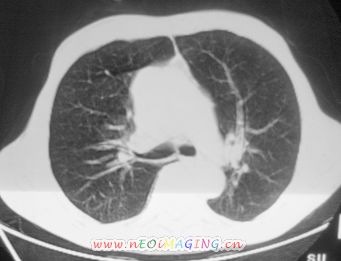

以下是引用卜一在2007-10-7 9:38:00的发言:[br]左下肺胸膜下团片影,内见含气支气管像,临近胸膜未见增厚。多考虑:1 左下肺炎症,建议消炎后复查!2 不除外肺隔离症合并感染!